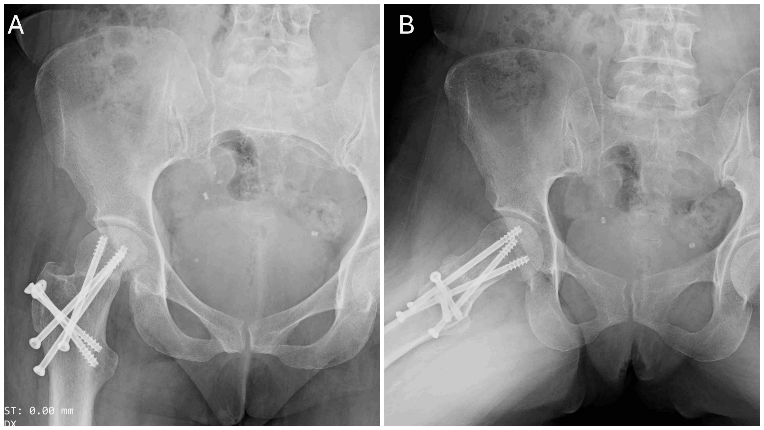

Figure 4: Image showing immediate post-operative X-ray (a) anteroposterior and (b) lateral view of right hip.

Sutures were removed after 2 weeks, and the wound had healed well. The patient was followed up monthly for the first 6 months, and then every 3 months up to 1 year. Partial weight-bearing was initiated at 8 weeks, progressing to full weight-bearing by 12 weeks, at which point complete fracture union was achieved (Fig. 5).

Figure 5: Post-operative X-ray at 3 months showing union at femoral neck fracture (a) anteroposterior and (b) lateral views.

At the 18-month follow-up, there were no signs of avascular necrosis of the femoral head, and the patient was able to walk comfortably with a good range of motion, and the patient’s Harris Hip Score was 96.80, signifying an excellent functional outcome (Figs. 6 and 7).